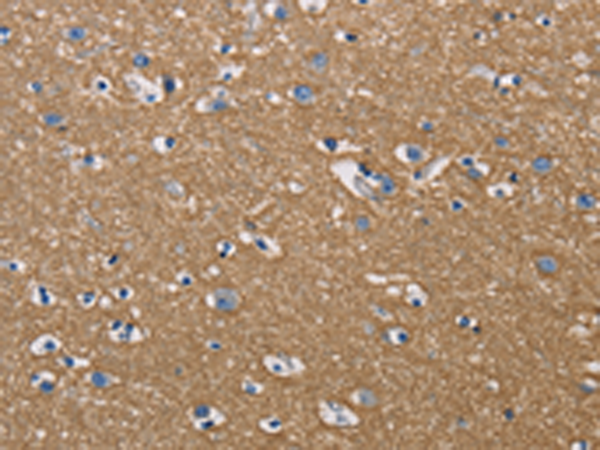

分类: 科研抗体货号: P08016别名: CBR; hCBR1; SDR21C1应用: WB,IHC反应种属: Human, Mouse, Rat